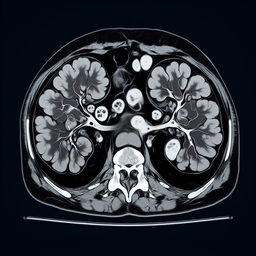

МРТ наднирників

Магнітно-резонансна томографія (МРТ) наднирників – це неінвазивне обстеження, яке дозволяє отримати детальні зображення цих залоз, що розташовані над нирками.